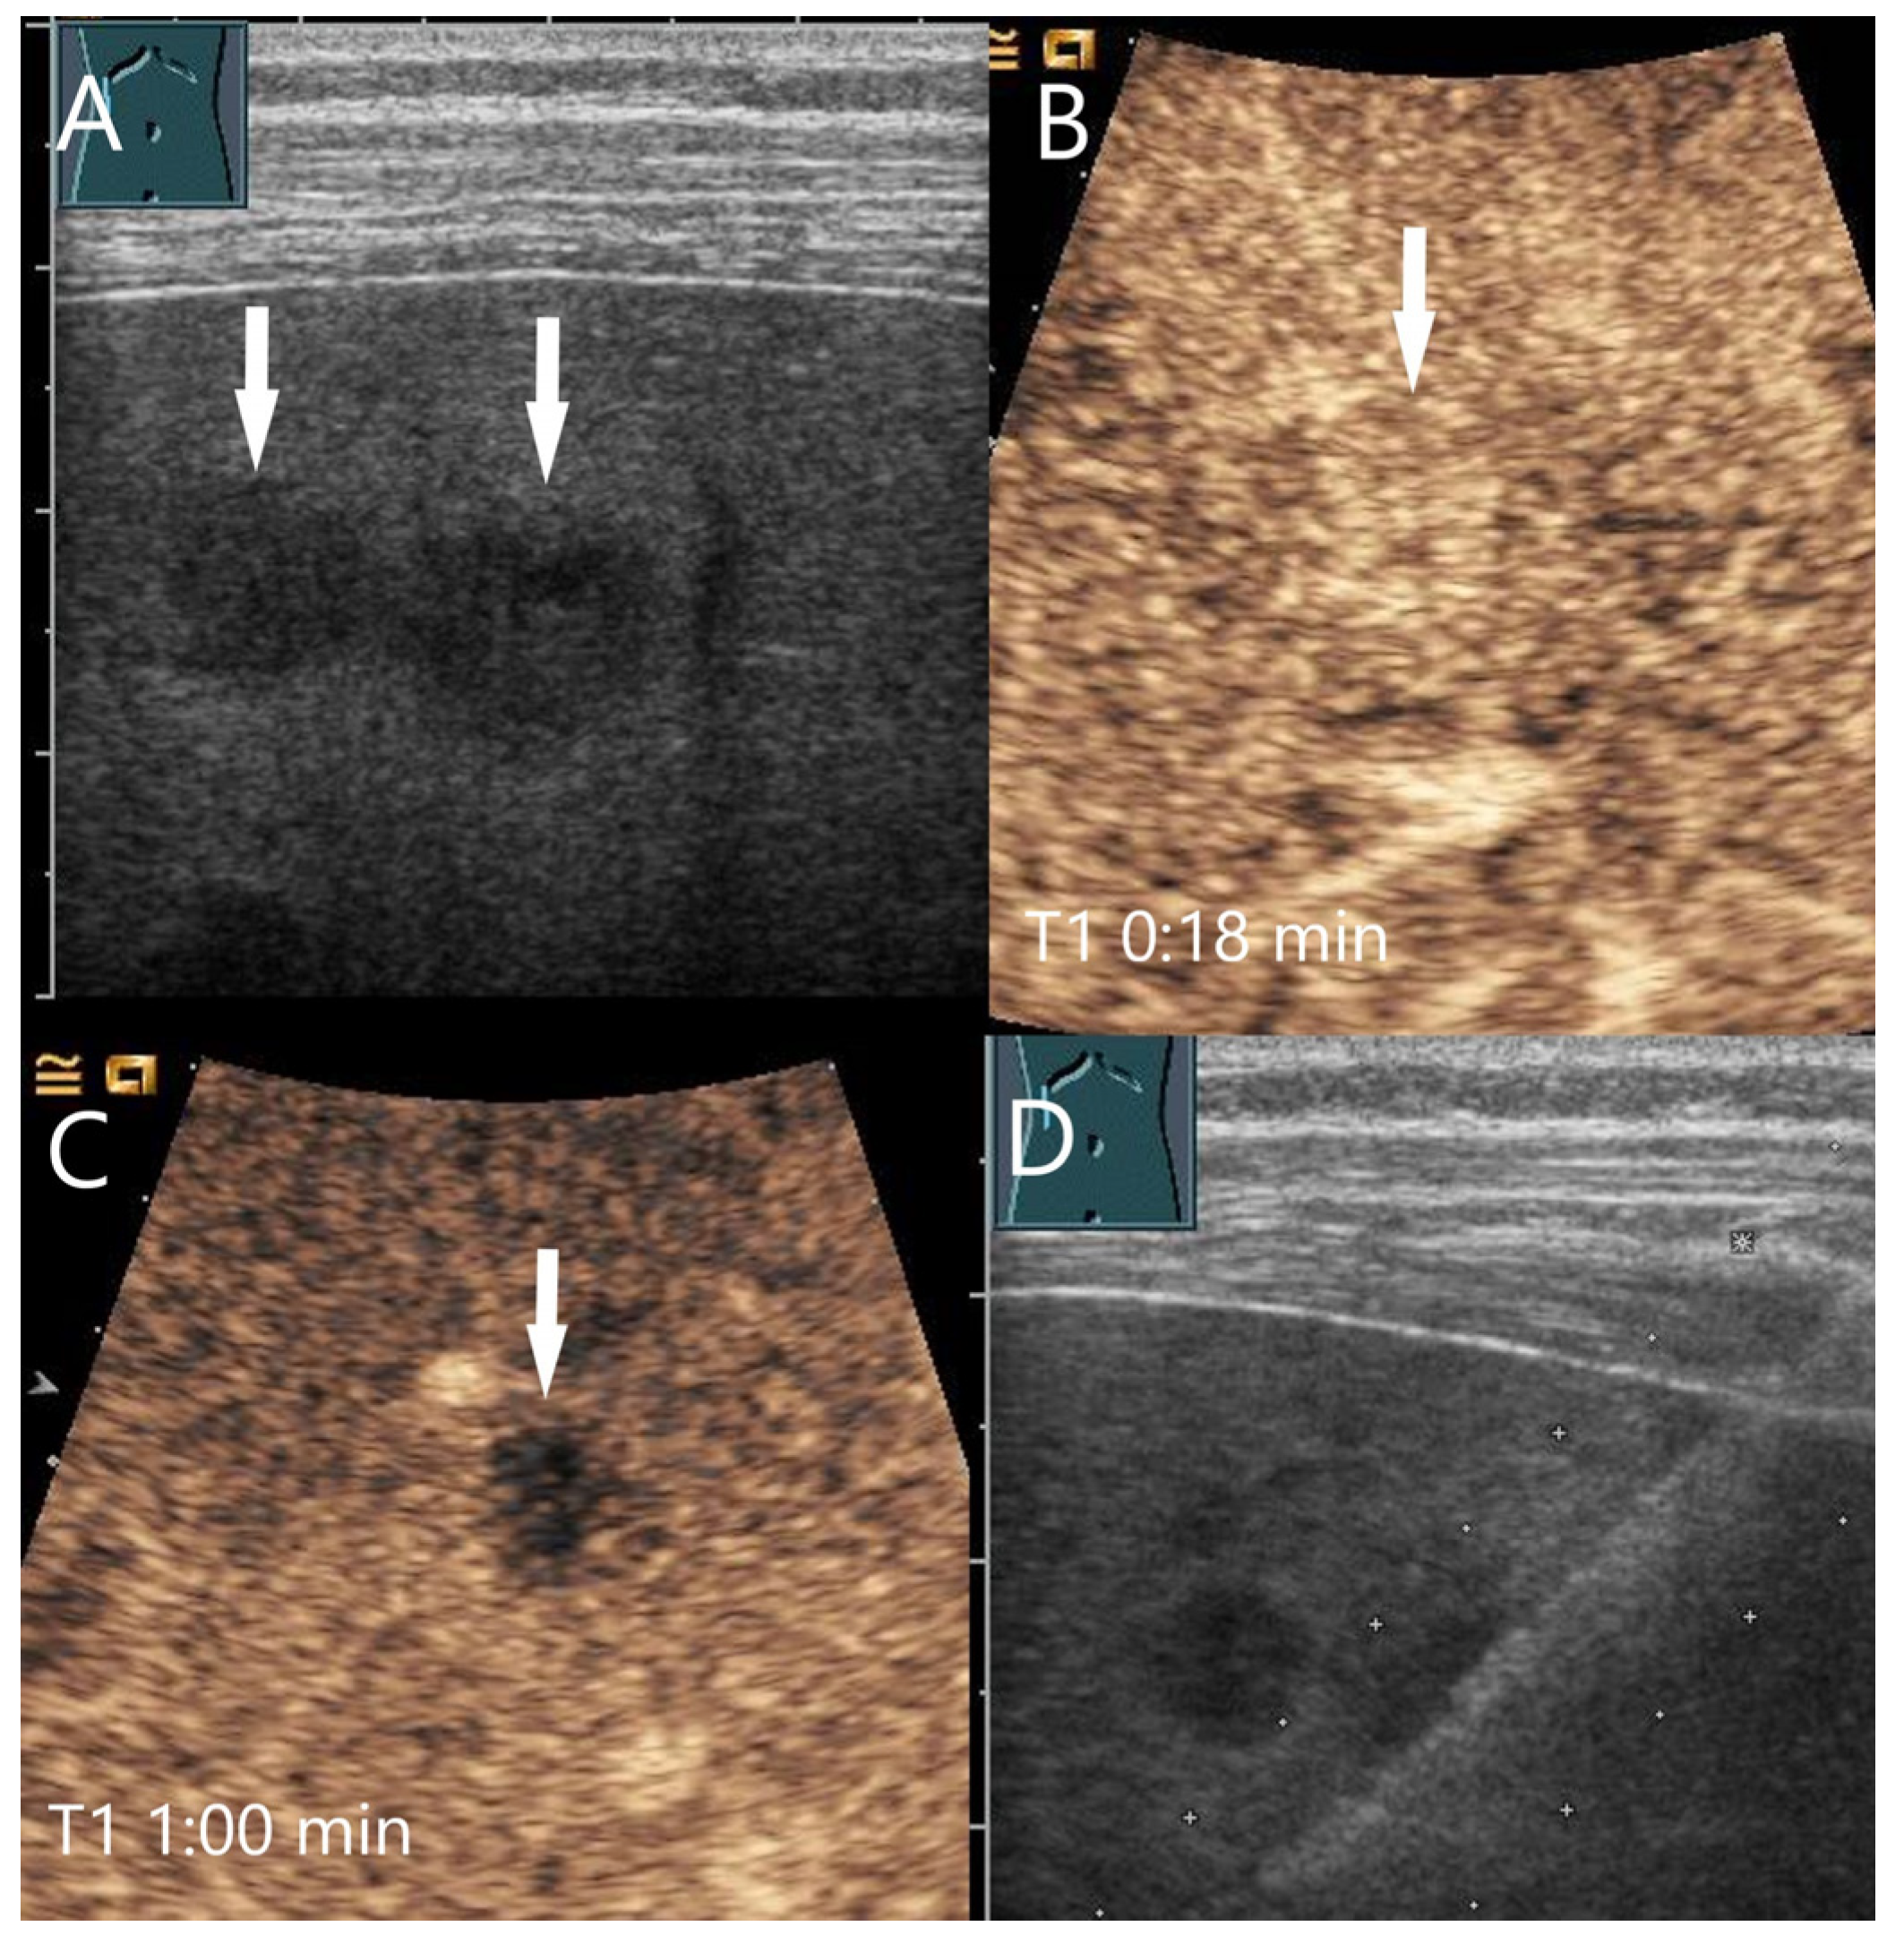

| Peliosis | Heterogeneously hypoechoic, well-defined margins, irregular shapes | Often hyperenhanced in the AP | Hypoenhancement in PVP or LP | Post sinusoidal outflow obstruction. |